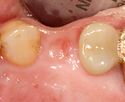

A healing abutment is attached to the implant fixture and the gingiva flap is sutured around the healing abutment.

A healing abutment is attached to the implant fixture, and the flap of gingiva is sutured around the healing abutment.